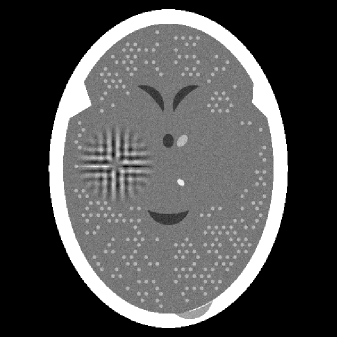

We used the Superiorized Version of the Basic Algorithm, as described in Subsection 5.2.2 to generate a sequence until it reached and considered that to be the output of the SM. We know that this output must exist for our problem and that its constraints-compatibility will not be greater than that of the output of the PSM. The computer time required to obtain this output was 102 seconds, which is over twenty times shorter than what was needed by the PSM to get its output. The TV of the the SM output was 876, which is also less than that of the output of PSM. The SM output is shown in Figure 2(b).

As summarized in Table 1, with the stopping rule that guarantees that the output of the SM is at least as constraints-compatible as the output of the PSM, the SM showed superior efficacy compared to the PSM: it obtained a result with a lower TV value at less than one twentieth of the computational cost.